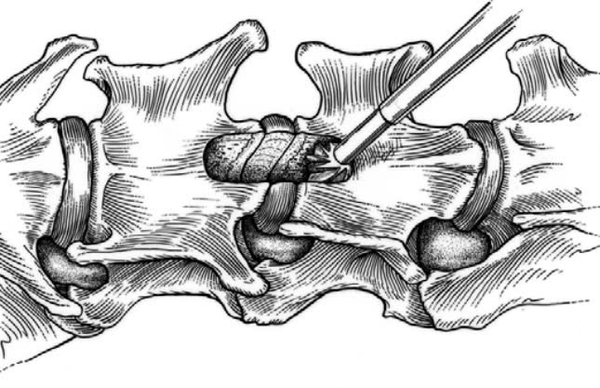

Giải phẫu sâu hơn:

Cuối cùng, cần lưu ý rằng cơ dài cổ có hướng chạy chéo từ phía sau ra phía trước và bám vào các mấu giữa phía bụng của cột sống.

Sau khi xác định chính xác vị trí đốt sống cổ C3 và C4, tiến hành tách cơ dài cổ, từ đó bộc lộ rõ đĩa đệm C3 – C4, tạo điều kiện cho các bước phẫu thuật tiếp theo.